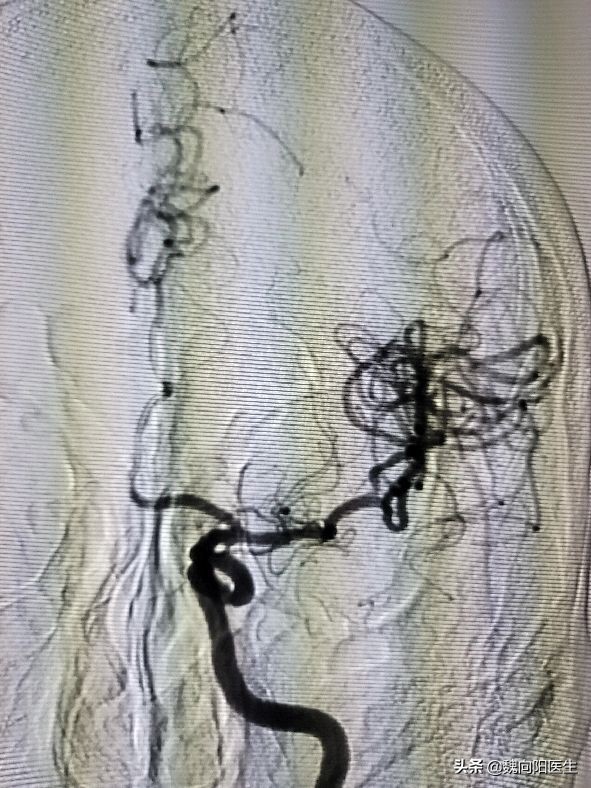

同时已经提前通知了那所医院的介入手术医生,给患者开通绿色通道,赶到医院之侯,直接推到导管室,准备脑血管造影开。

脑动脉血栓

由于时间很紧凑,没有时间全麻,在局麻状态下进行。手术很顺利,一把通(取栓支架到位之后,一把就把血栓带下来啦)。

闭塞的大脑中动脉又重新恢复了血流。这下患者的家属也松了一口气。